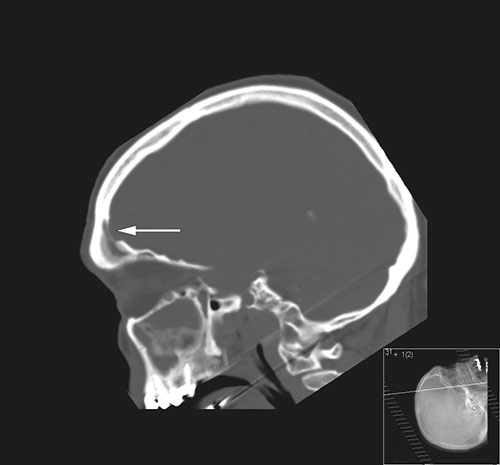

En mann i 60-årsalderen ble innlagt på lokalsykehus etter at han ble funnet konfus og med redusert bevissthet. Han hadde da ifølge komparentopplysninger hatt hodepine i to dager. Ved undersøkelse var han høyfebril (40,5 °C) og nakkestiv. Glasgow Coma Scale ble vurdert til 12. Den nevrologiske undersøkelsen var ellers upåfallende. Cerebral CT tatt med beinvindu i sagittalplan (bilde til venstre) viste fortetning i sinus frontalis og beindefekt (pil) inn mot epiduralrommet. Cerebral MR tatt med T1-vekting etter intravenøs kontrast (bilde til høyre) viste venstresidig subdural væskeeffusjon (hvit pil), kontrastladning i dura (rød pil) og signalforandringer (stjerne) i venstre frontallapp. Spinalvæsken var blakket med hvite blodceller på 2187 · 10⁶/l (normalt 0 – 5) og totalprotein på 1,55 g/l (normalt 0,15 – 0,50). På mistanke om subduralt empyem og cerebritt ble pasienten satt på antibiotika og overflyttet til universitetssykehus. Der ble han operert med kraniotomi og drenasje av empyem samt tetting av beindefekt i os frontale. Dyrkning av puss viste Streptococcus intermedius (Milleri).